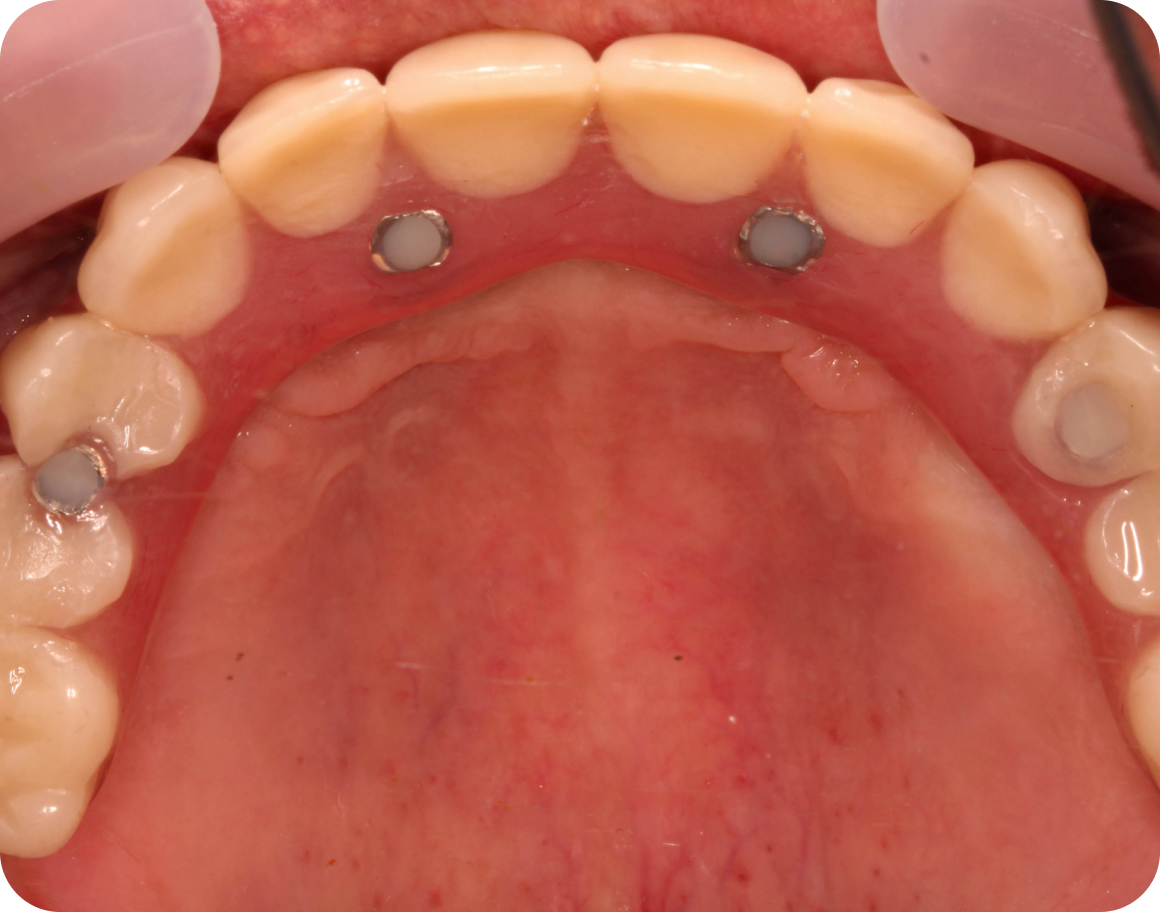

Установка имплантов

Устанавливаем импланты в правильную позицию в костной ткани, чтобы импланты служили максильно долго и не застревала пища между зубами

Установка временного протеза

В большинстве случаев мы устанавливаем временный протез на импланты в день операции. Но не всегда это возможно. Если кость слабая, и не удалось застабилизировать импланты, то устанавливаем временный съемный протез на имплантах

После приживления имплантов через 4-6 месяцев съемный протез переводится в несъемный